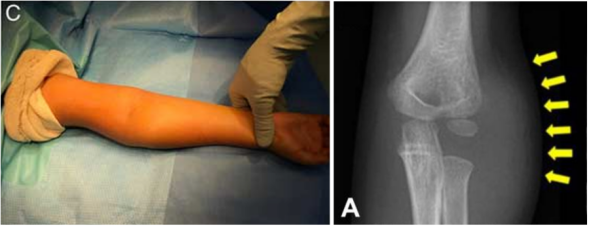

外侧骨赘

骨折愈合后,患儿常出现明显的外侧骨性隆起增生。作者强烈建议,临床医生应在启动治疗之初,即告知家属患儿术后可能出现外侧骨性隆起,而非待隆起形成、引发家长焦虑后再做解释。

图20: 一名 9 岁 8 个月女童,1 年 9 个月前因肱骨外髁韦氏 Ⅲ 型骨折接受切开复位内固定术A 正位 X 线片可见肘部外侧形成明显骨性隆起(骨棘);B 侧位 X 线片显示该骨性隆起无明显向前、向后延伸;C 患儿指认肘部外侧骨性隆起的临床照片;D 医师指认该骨性隆起的临床特写照片;该骨性隆起仅予临床观察随访,未行手术干预。